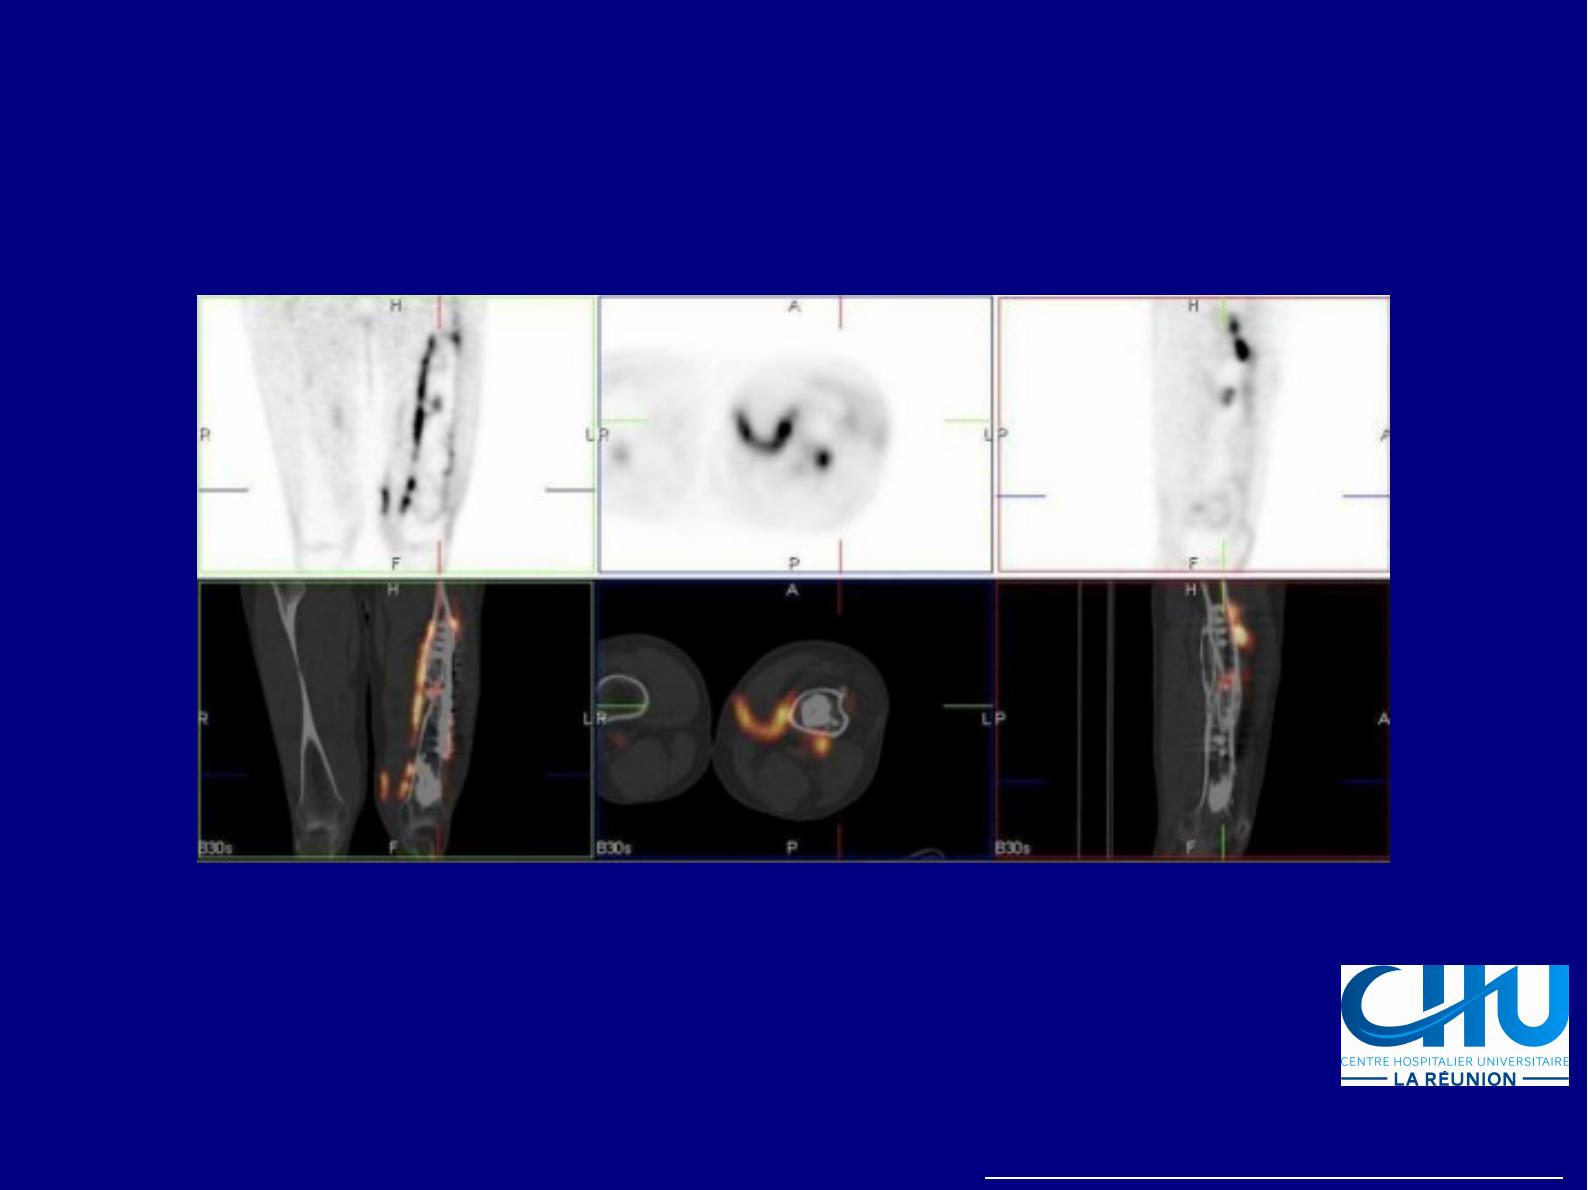

Van der Bruggen et al, 2010, Semin Nucl Med 40:3-15